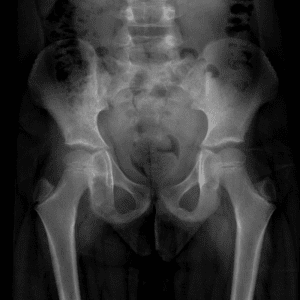

Pediatric Radiographs